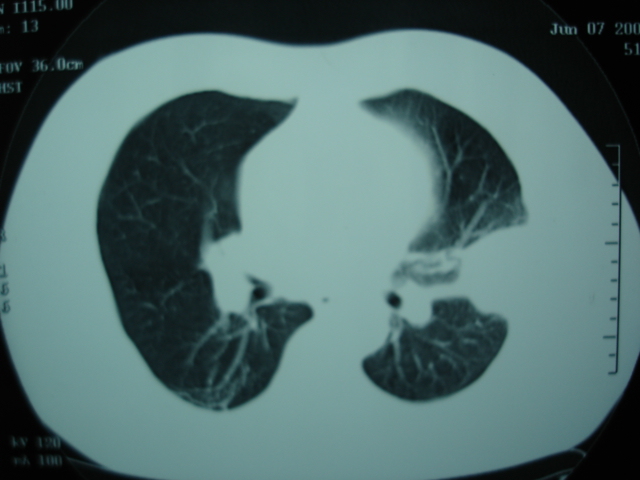

2009.6.4 2009.6.7 2009.8.21

第三次ct2009.8.21